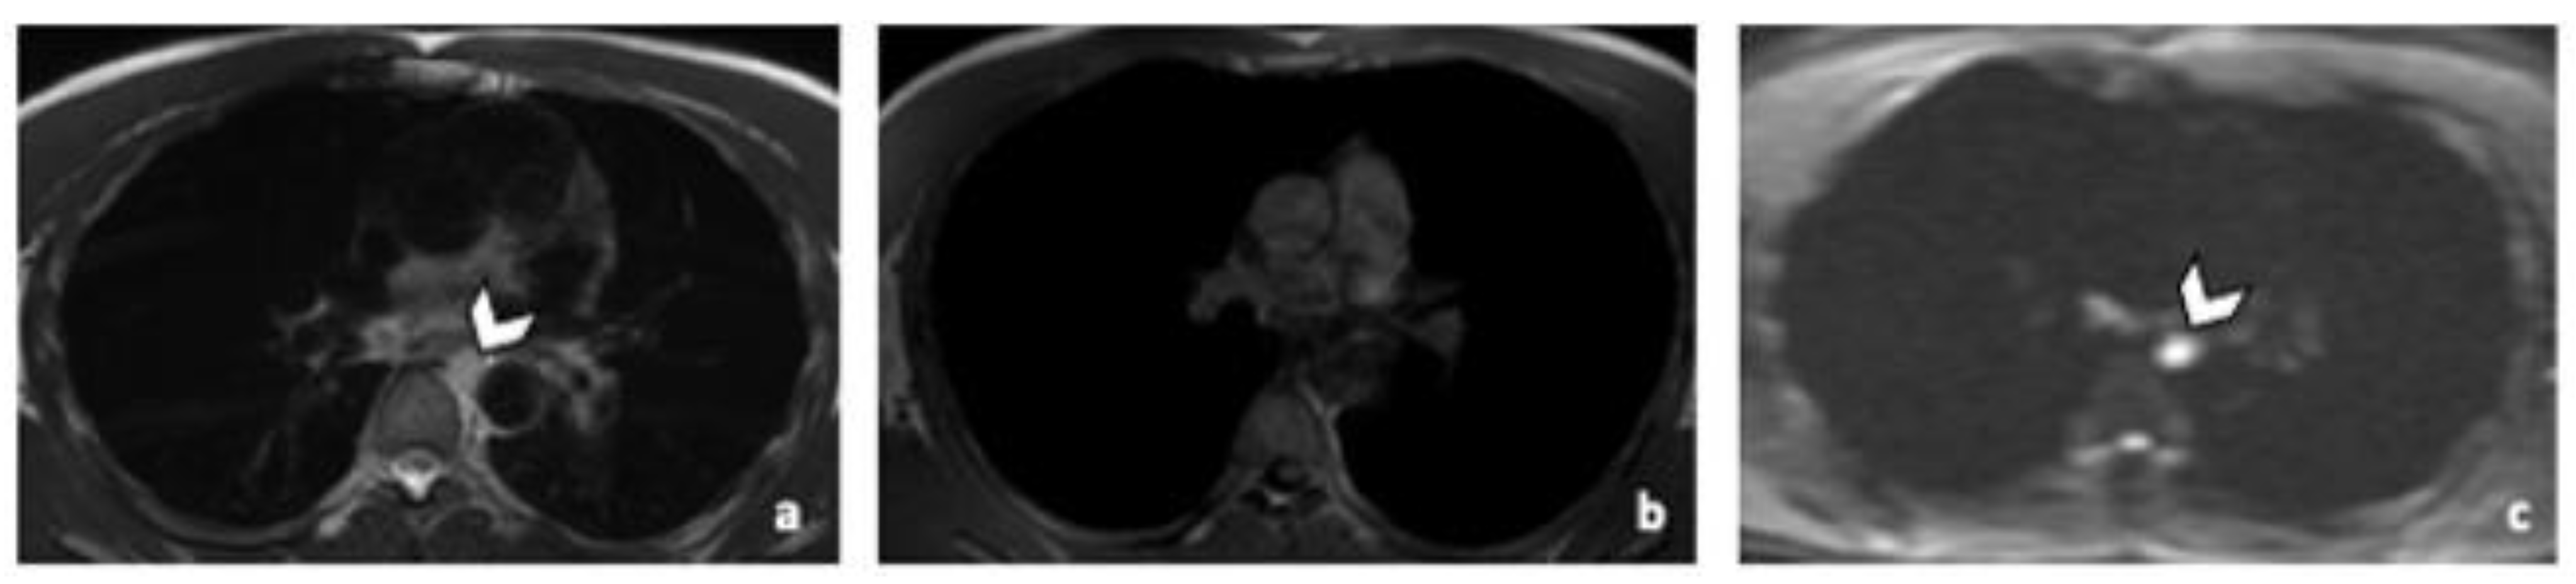

Figure 4.

Comparison of WB sequences in a 39-year-old patient with NSGCC. Axial T2-weighted (a), 3D T1 GRE In Phase (b) and high b-value DWI (b = 1000 s/mm2) MR images. One of the readers missed an enlarged paraoesophageal lymph node (arrowhead) demonstrating a high signal intensity in T2 (a), barely visible in T1 and presenting a restricted Diffusion (c). Abbreviations: NSGCC: Non-Seminomatous Germ Cell Cancer, 3D: Three Dimensional, T1 GRE: T1 Gradient Echo, DWI: Diffusion Weighted Imaging.